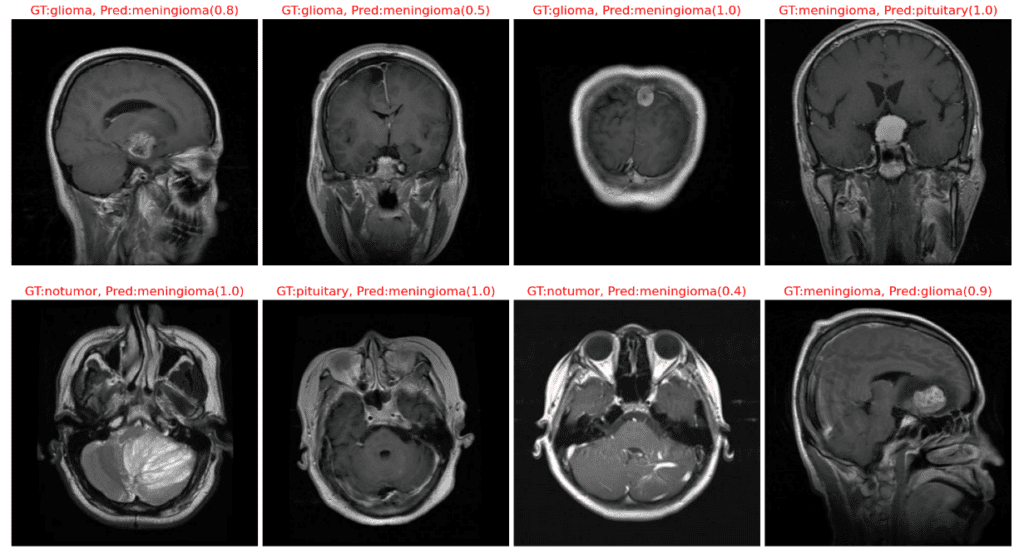

The following plot displays instances where our model has misclassified the image samples.